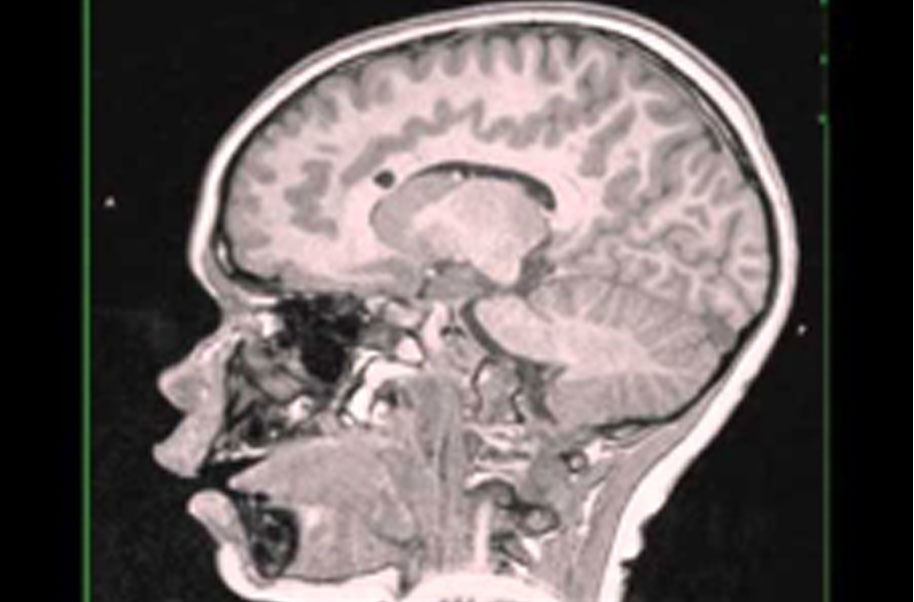

Subependymal giant cell astrocytoma (sega, sgca, or sgct) is a low-grade astrocytic brain tumor (astrocytoma) that arises within the ventricles of the brain. It is most commonly associated with tuberous sclerosis complex (tsc).

Subependymal giant cell astrocytomas (sgcas or alternatively segas) are benign tumours (who grade i), seen almost exclusively in young patients with tuberous sclerosis. They can be either asymptomatic or symptomaticdue obstructive hydrocephalus, surgery treatment is oftencurative.